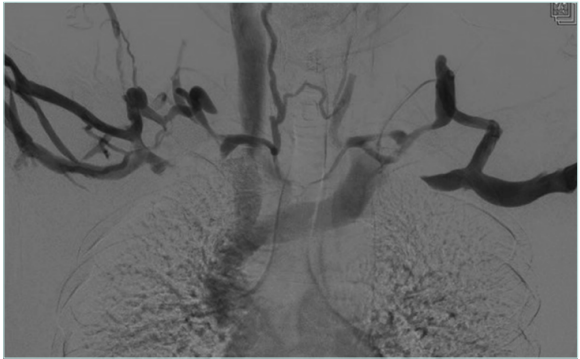

Figure 3. Venogram of arms in neutral position with postthrombotic syndrome (PTS) on the right side and no venographic signs of venous obstruction on the left side.

Figure 4. Venogram for arms in abduction position showing subclavian vein compression on both sides.